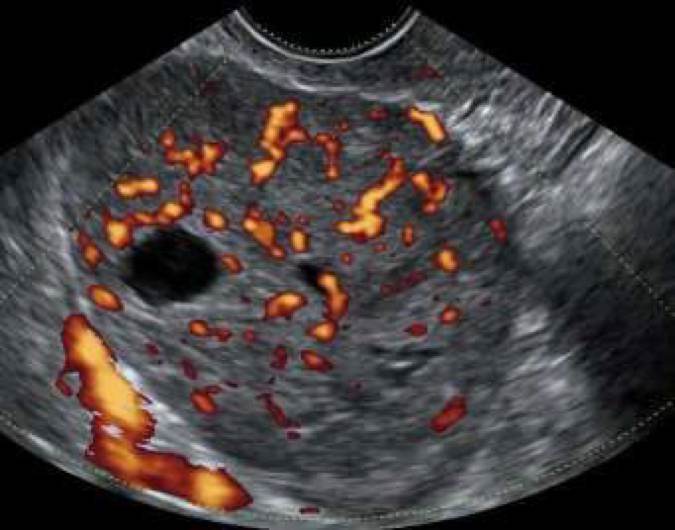

Det är relativt vanligt förekommande med metastaser i ovarierna från andra maligna tumörer, vanligast förekommande är metastaser från kolorektal, övre GI, ventrikel, lymfom och bröstcancer. Det finns studier som har visat att metastaser från lymfom, bröst-, och ventrikelcancer ofta är solida medan metastaser från colorektal, gallblåse, pancreascancer ofta är flerrummigasolida med inslag av nekros 10,11 (Bild 9-12). Vid spridd bukmalignitet kan vara svårt att tala skilja primär ovarialcancer från metastaserade cancer av annan genes, inslag av tumörnekros, avsaknad av ovarialtumör talar dock för icke ovariell genes. Transvaginal eller transabdominell mellanålsbiopsi är en snabb enkel minimal-invasiv metod att fastställa tumörens primaritet.

Bild 9. Coloncancermetastas hos 19 årig kvinna i HNPCC familj.

Bild 10. "Krukenberg tumör", ventrikelcancermetastas

Bild 11. Flerrummig solid pancreascancer metastas.

Bild 12. Solid bröstcancer metastas